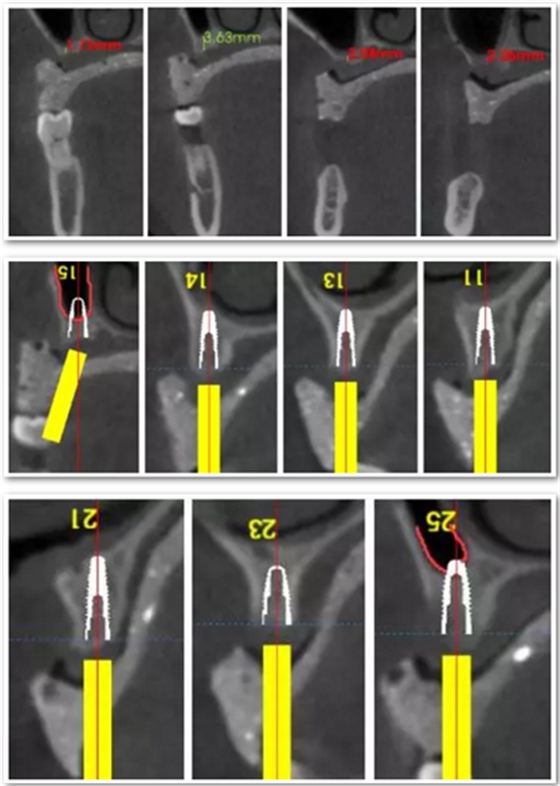

患者骨高度嚴(yán)重不足,尤其是后牙區(qū),骨高度基本都只有2mm。按常規(guī)傾斜植入的方式也不可行,因此選擇在5號位通過內(nèi)提升方式植入植體。

手術(shù)時,帶上導(dǎo)板,逐級備孔,在15和25的位置需要進(jìn)行內(nèi)提升,因此對于備孔深度的把控尤為重要,導(dǎo)板的作用得到了重大發(fā)揮。